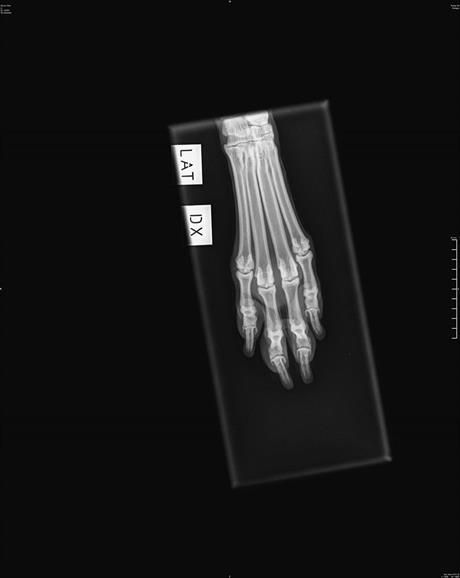

Röntgen

Hos oss röntgar vi med digital framkallning. Prisexempel: Höfter och armbågar 1900:-, endast höftleder 1400:- tillkommer gör SKK's avgift för avläsning och registrering.

OBS!

Innan röntgen måste remiss beställas via följande länk:

https://www.skk.se/sv/uppfodning/halsa/halsoprogram/bestall-rontgenavlasning/

Där står all information om tjänsten och hur man gör för att beställa röntgenavläsning.

Remissen kan inte beställas och betalas vid röntgentillfället utan ska skapas minst ett dygn före

röntgen.